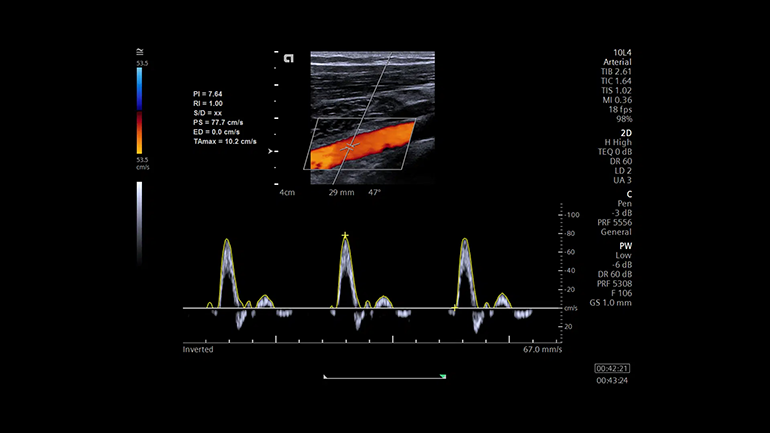

Технология автоматизации процесса измерений в 2D-, M- и допплеровских режимах eSie Measure. Технология eSie Measure позволяет выполнять количественные измерения одним нажатием кнопки, тем самым сокращается количество ручных действий врача-диагноста и повышается воспроизводимость результатов.

Технология автоматизации процесса измерений в 2D-, M- и допплеровских режимах eSie Measure. Технология eSie Measure позволяет выполнять количественные измерения одним нажатием кнопки, тем самым сокращается количество ручных действий врача-диагноста и повышается воспроизводимость результатов. Технология автоматических перинатальных измерений eSie OB. eSie OB автоматизирует выполнение биометрических измерений при акушерских исследованиях. Она не только уменьшает время сканирования и сокращает количество нажатий клавиш, но и повышает воспроизводимость УЗ- исследований.